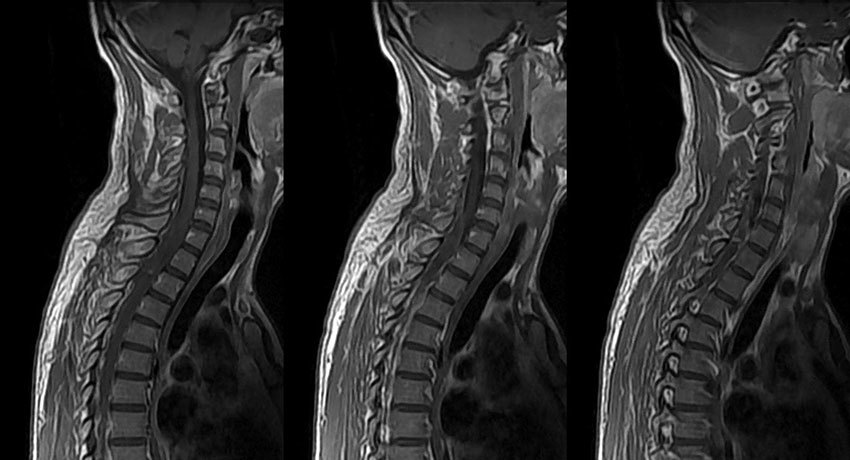

МРТ шейного отдела позвоночника

Магнитно-резонансная томография шейного отдела позвоночника — высокоинформативный метод диагностики, с помощью которого можно выявить различные патологии позвонков, межпозвоночных дисков, спинного мозга, нервов и других мягких тканей, кровеносных сосудов.

Во время МРТ, в отличие от КТ и рентгенографии, не применяется рентгеновское излучение, поэтому данное исследование более безопасно и имеет меньше противопоказаний. В то время как компьютерная томография обеспечивает более качественную визуализацию костных структур, МРТ более предпочтительна для исследования мягких тканей. В онкологии ее часто применяют для диагностики метастазов и первичных опухолей головного, спинного мозга.

Что показывает МРТ шейного отдела позвоночного столба?

Магнитно-резонансную томографию шеи можно применять для диагностики широкого спектра различных патологий:

Метастазы и первичные опухоли в позвонках, спинном мозге, окружающих мягких тканях.

Деформации позвоночника.

Дегенеративные процессы в позвоночном столбе, межпозвоночные грыжи.

Аномалии развития шейного отдела позвоночника.

Сдавление спинного мозга, спинномозговых нервов.

Инфекционно-воспалительные процессы в позвонках и окружающих тканях, абсцессы (полости с гноем).

Гемангиомы в телах позвонков — патологические образования, состоящие из расширенных сосудов.

Патологии артерий и вен шеи.

Иногда, для того, чтобы лучше изучить те или иные структуры, проводят МРТ с контрастированием. Перед исследованием или в течение него пациенту внутривенно вводят контрастный препарат на основе металла гадолиния. В частности, это бывает необходимо, когда нужно обнаружить опухолевые очаги.